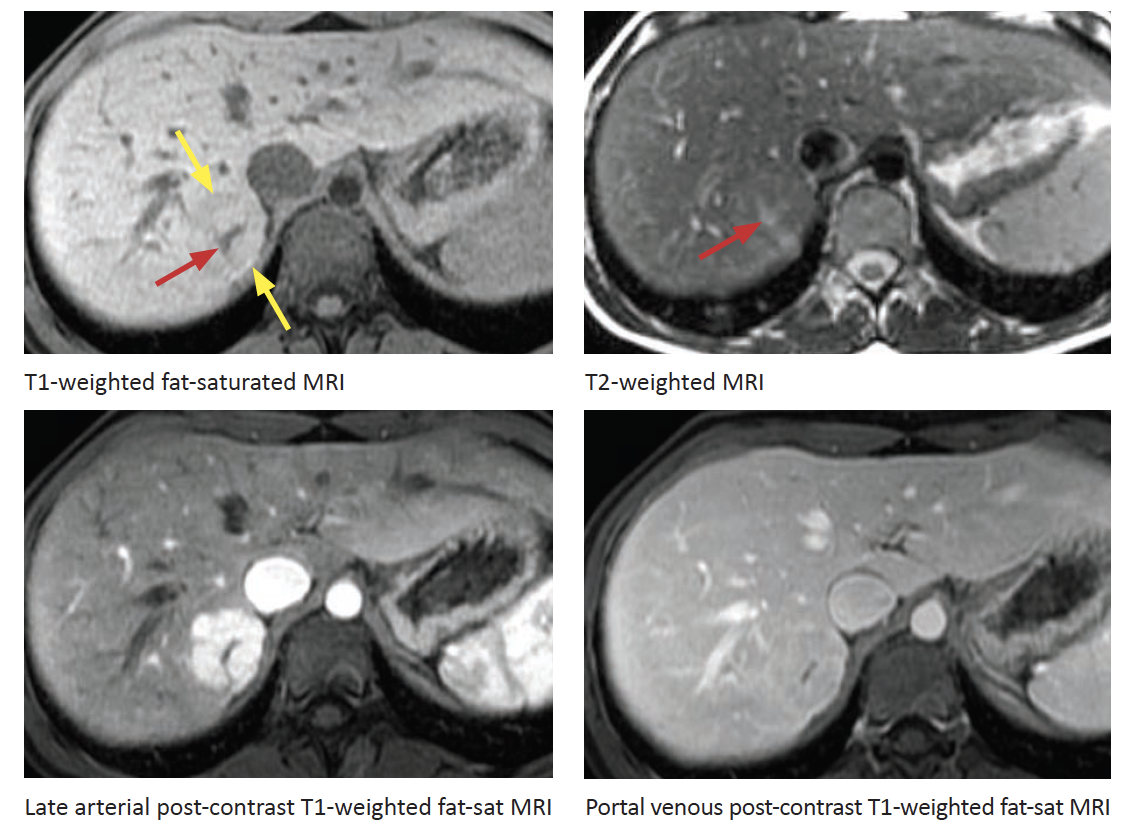

Dx?

FNH

Arterial enhancement with quick wasout

Scar is T2 hyperintense. Delayed enhancement of the scar is not shown here

Hemangioma

Note the two areas of nonehnacement on the delayed images consistent with cystic degeneration